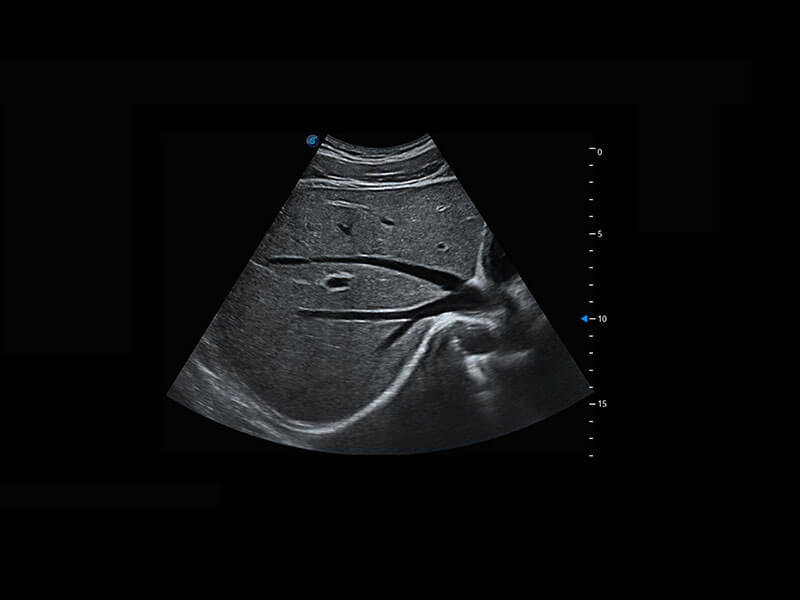

新生儿脊髓圆锥

新生儿心脏